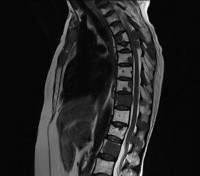

О наличии онкологического заболевания свидетельствует положительный анализ крови на онкомаркеры. На начальном этапе диагностики больным с подозрением на метастазы в позвоночник назначают рентгенографию позвоночника. На ранних стадиях метастазирования рентгенологические признаки поражения позвонков могут отсутствовать, поэтому при отрицательном результате исследования пациентов с подозрением на метастазы в позвоночник направляют на сцинтиграфию, КТ и МРТ позвоночника. Для выявления первичной неоплазии и вторичных очагов проводят УЗИ органов брюшной полости, рентгенографию органов грудной клетки, маммографию и другие диагностические процедуры.

Метастазы в позвоночник. Вторичное злокачественное поражение позвоночного столба, возникающее при миграции опухолевых клеток из очага, расположенного в другом органе. Проявляются болями, нарушениями чувствительности и движений, парезами, параличами, тазовыми расстройствами, гиперкальциемией и патологическими переломами. Диагноз «метастазы в позвоночник» устанавливают с учетом анамнеза, общего и неврологического осмотра, рентгенографии позвоночника, КТ позвоночника и других диагностических процедур. Лечение - химиопрепараты, радиотерапия, гормональная терапия, ламинэктомия, стабилизирующая операция.